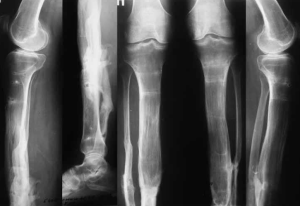

Влияние полиморфизма генов IL-17A и PPARG на течение гнойных осложнений после лечения пострадавших с травмами костей нижних конечностей

Цель работы — определить влияние полиморфизма генов IL-17A и PPARG на течение гнойных осложнений после лечения пострадавших с травмами костей нижних конечностей.

острые травматические повреждения коленного сустава, голени, голеностопного сустава и стопы (переломы, вывихи, разрывы связок) в анамнезе;

наличие гнойно-воспалительных осложнений (остеомиелит, гнойный артрит, флегмона, абсцесс), развившихся в процессе лечения и в течение первого года после лечения;